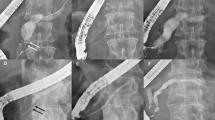

This retrospective multicenter study was conducted at eight tertiary centers in Taiwan, and it was approved by the Research Ethics Review Committees of the study institutes (Far Eastern Memorial Hospital FEMH-111171-E, China Medical University Hospital CMUH111-REC2-114, Kaohsiung Chang Gung Memorial Hospital 202201132B0D001, Changhua Christian Hospital CCH210103, Fu Jen Catholic University Hospital FJUH111205, and Shin Kong Wo Ho-Su Memorial Hospital 20221012R). All study methods were performed in accordance with the Committee on Publication Ethics guidelines. Codes rather than identifying information of the enrolled patients were used in this retrospective study, and the requirement for written informed consent was waived (Research Ethics Review Committee of Far Eastern Memorial Hospital). All data generated or analyzed during this study are included in this published article and its supplementary information files. Patients with AP who developed symptomatic PFCs and were treated by internal drainage with EUS-guided transmural LAMS placement (Figs. 1, 2, 3 and 4) between June 2019 and May 2023 were enrolled consecutively. All procedures were performed by endosonographers with more than 5 years of experience.

In this study, we used Hot AXIOS™ electrocautery-enhanced LAMSs (Boston Scientific, Marlborough, MA, USA) for internal drainage. The Hot AXIOS™ is a saddle-shaped braided flexible metal stent which is flanged at both ends and is fully covered by a silicon membrane. The sizes of the PFCs, defined as the proportion of necrotic area in WON, and the distance between the wall of the encapsulated PFC and gastrointestinal tract, were evaluated by EUS. Color Doppler was used to avoid intervening vessels at the puncture site and trajectory. Under EUS-guidance, an electrocautery-enhanced delivery system was deployed (autocut mode, 100 W, effect 5, VIO200D, ERBE, Germany) from the gastrointestinal lumen into the PFC, and then the bilateral flanges were deployed in order to approximate the PFC and gastrointestinal wall. After endoscopic and fluoroscopic confirmation of the iatrogenic communicating tract created by the LAMS, the delivery system was removed. If clinical indications were present, such as persistent PFC-related symptoms after LAMS placement, transoral direct endoscopic necrosectomy (DEN) using foreign body retrievers was performed through the LAMS to remove necrotic tissues in the pancreatic WON. The LAMS was removed if PFC-related clinical symptoms resolved, and double-pigtail plastic stents (DPSs) were inserted via cysto-gastroenterostomy at the discretion of the endoscopist. Once the diagnosis of disconnected pancreatic duct syndrome (DPDS) was confirmed, transmural DPSs were inserted via cysto-gastroenterotomy or transpapillary pancreatic stenting if possible after removal of LAMS.